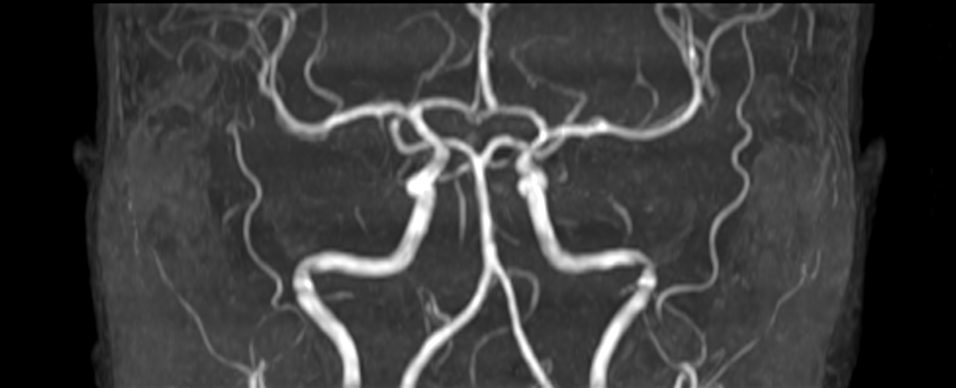

Coronal 3D Inflow